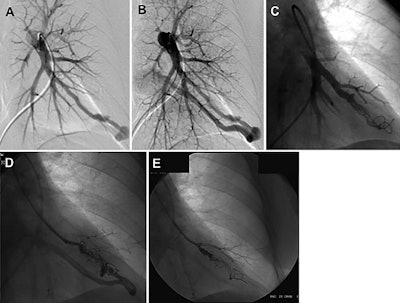

Interventional radiology treatment with an endovascular embolization technique has emerged as an effective therapy for pulmonary AVMs, using a variety of coils and plug-like devices that are placed at the site of a malformation under imaging guidance. But such procedures can be undermined by persistence, the term for when a connection is re-established between a vein and artery despite treatment to block the interface.

Smokers, in particular, have a higher likelihood of persistence following endovascular treatment for AVMs, the authors noted. Smoking contributes to inflammation by disrupting vascular angiogenesis, and remodeling and promoting the chance of thrombosis. Chemicals in tobacco smoke can also contribute to oxidative stress that predisposes patients to vessel wall injury and accelerated atherosclerosis.